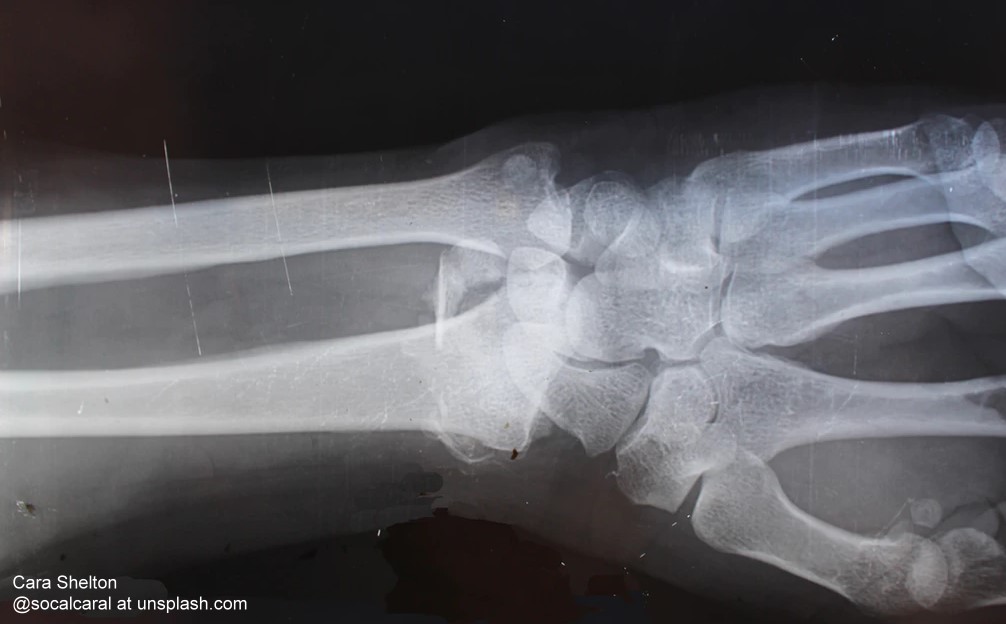

Klettern, toben, Skateboard fahren: Am häufigsten brechen sich Kinder und Jugendliche den Arm in der Nähe des Handgelenks – den sogenannten distalen Unterarm [1]. Die Diagnose dieser Verletzung erfolgt üblicherweise durch eine Röntgenuntersuchung – dabei ist Ultraschall genauso zuverlässig. Eine Expertengruppe unter Beteiligung mehrerer Mitglieder der Deutschen Gesellschaft für Ultraschall in der Medizin e.V. (DEGUM) hat eine Methode evaluiert, die rund 81 Prozent der Röntgenuntersuchungen bei Kindern mit Verdacht auf eine distale Unterarmfraktur einsparen könnte. Aufgrund der potenziell schädlichen Wirkung sollten Kinder so selten wie möglich der ionisierenden Strahlung ausgesetzt werden. Die Ergebnisse haben die Autoren der Studie in der Fachzeitschrift Ultraschall in der Medizin vorgestellt [2].

Kinder, die sich in der Wachstumsphase befinden, nehmen während einer Röntgenuntersuchung eine fünfmal höhere Dosis der schädlichen ionisierenden Strahlung auf als Erwachsene. Aus diesem Grund sollten unnötige Untersuchungen so weit wie es nur geht verhindert werden. „Der so genannte Wrist-SAFE-Algorithmus ist ein wirksames Mittel, die Strahlenbelastung bei Kindern auf das absolut notwendige Minimum zu reduzieren“, sagt Dr. med. Kay Großer, Chefarzt der Klinik für Kinderchirurgie und Kinderurologie am Helios Klinikum Erfurt, einer der Autoren der Studie und zugleich stellvertretender Leiter der Sektion Pädiatrie der DEGUM. Mit Hilfe des Algorithmus könnte nach Berechnung der Studie jährlich allein in Deutschland fast 285.000 Röntgenuntersuchungen bei Kindern eingespart werden. Die Studie knüpft an Erkenntnisse vorangegangener Untersuchungen an, nach denen der Ultraschall bei Verdacht auf eine Fraktur in vielen Fällen eine ebenso zuverlässige Diagnose ermöglicht wie das Röntgenbild und in manchen Fällen sogar überlegen ist, gerade im Fall von Knochenbrüchen [3, 4].

An der jetzt vorgestellten prospektiven multizentrischen Phase-IV-Studie unter dem Titel Sokrates II beteiligten sich Ärztinnen und Ärzte aus Kliniken in Bochum, Krakau, Erfurt, Neuss und Düsseldorf. Im Zeitraum zwischen November 2012 und November 2014 untersuchten sie insgesamt 498 Patienten im Alter von null bis zwölf Jahren. Alle kamen mit Schmerzen im Unterarm nahe dem Handgelenk in Folge eines Traumas in die Klinik. Ausschlusskriterien für eine Untersuchung nach dem Wirst-SAFE-Algorithmus waren offene Frakturen oder Wunden, ein Verdacht auf Gefäß- oder Nervenverletzung sowie ähnliche Frakturen in den beiden Vorjahren. Trafen diese Kriterien nicht zu, erfolgte eine Diagnosestellung anhand von Sonografiebildern an sechs vordefinierten Positionen rund um den Unterarm. In 321 Fällen stellten die Ärztinnen und Ärzte auf diesem Weg die sichere Diagnose Fraktur. Nur in 58 Verdachtsfällen war eine Röntgenuntersuchung zur Kontrolle notwendig, die das Ergebnis des Ultraschalluntersuchung allerdings in 57 Fällen bestätigte. „Die Sonografie liefert bei Vorgehen nach Wrist-SAFE treffsichere Ergebnisse und sollte vor allem bei Kindern das Mittel der Wahl sein“, sagt Großer.